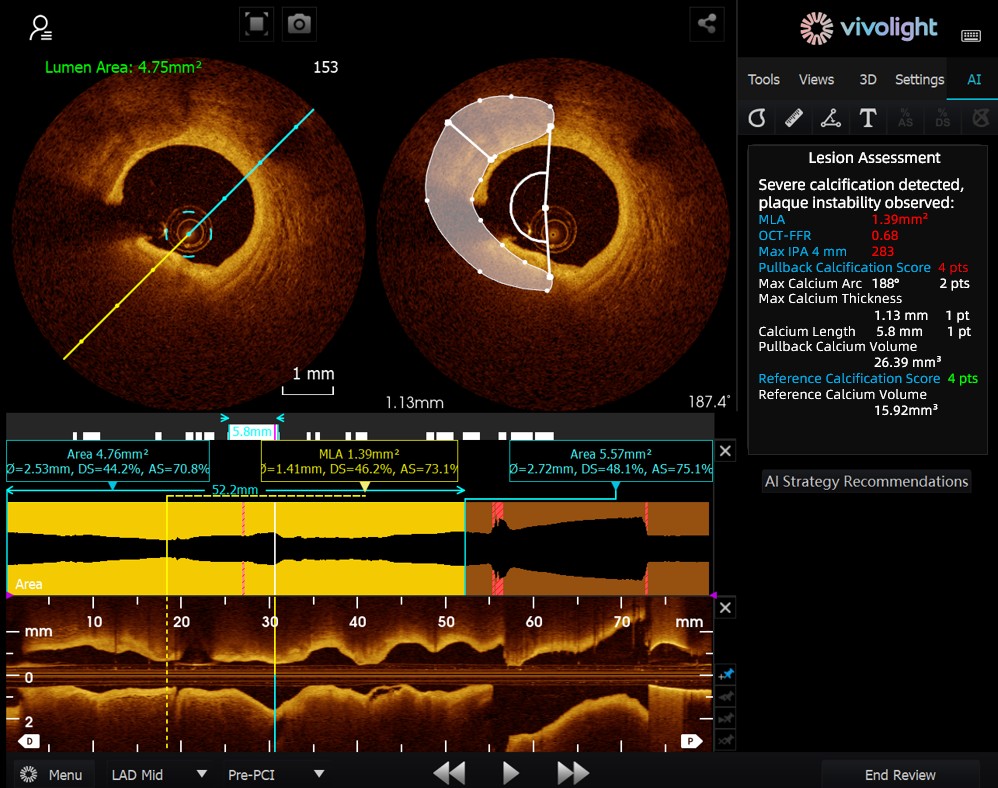

Sviluppato sulla base del sistema OCT di Vivolight Medical, AI-OCT è un sistema intelligente di supporto decisionale di nuova generazione per l'imaging intravascolare. Integra dati diagnostici di imaging intravascolare sparsi, tra cui diametro del lume, lesioni colpevoli, OCT-FFR e natura della placca, in strategie di trattamento complete e raccomandazioni attuabili. In quanto software di ricerca indipendente integrato nella piattaforma OCT, è sviluppato in collaborazione con diversi ospedali per creare versioni personalizzate su misura per specifiche esigenze cliniche.

Durante il forum all'avanguardia, gli esperti hanno sottolineato che il sistema AI-OCT rappresenta un passaggio radicale dalla "visualizzazione di immagini" alla "fornitura di piani di trattamento", affrontando le sfide del sovraccarico di informazioni e della complessità del processo decisionale nelle procedure interventistiche cardiache, che tradizionalmente si basano in larga misura sull'esperienza del medico. I principali vantaggi del sistema includono:

●Guida intraoperatoria in tempo reale: Organizza in modo dinamico le informazioni diagnostiche durante l'intervento chirurgico, fornendo parametri chiave e raccomandazioni cliniche.

●Processo decisionale basato sulle prove: Tutti i suggerimenti sono in linea con il consenso degli esperti e con le linee guida cliniche, garantendo rigore e affidabilità.

●Tracciabilità completa: Un database dinamico supporta ogni raccomandazione, con documentazione completa per garantire trasparenza e sicurezza.

Il sistema AI-OCT adotta un'architettura "piccolo modello + big data + grande modello": i modelli piccoli consentono un'interpretazione precisa delle immagini, mentre i modelli grandi consentono un ragionamento clinico completo. Sfruttando database cardiovascolari di alta qualità e la tecnologia RAG (Retrieval-Augmented Generation), offre un supporto end-to-end, dalla valutazione della lesione allo sviluppo della strategia di trattamento.